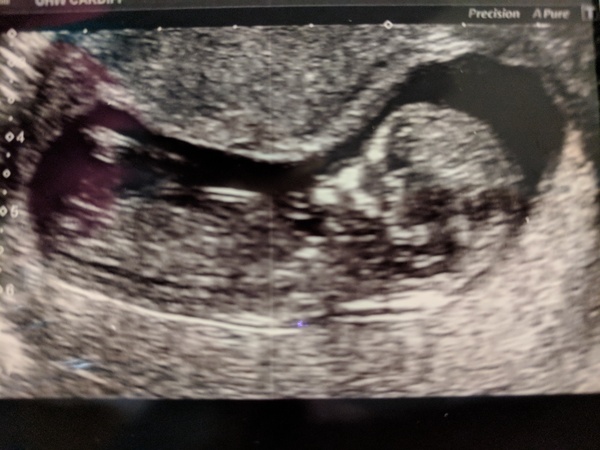

Flamingo84 · 21/02/2018 22:02

Had my scan today at 12+3. And another new due date of 2 Sept! I’m letting myself be excited now I know all is ok. 😀

@Flamingo84 Love your photo!

Beautiful scan @Flamingo84